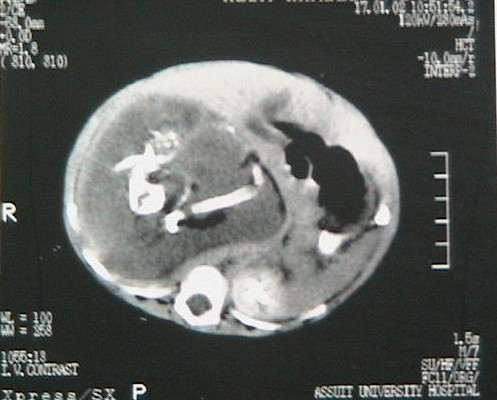

Доктор Аджей Мехта ще го посрещне през 1999 година На пръв взор е мислил, че става въпрос за израстък, който ще се пръсне и предложил незабавно да се направи интервенция. След разрязването на стомаха в операционната зала, вместо израстък, от него изтича прекалено много течност, а с надникването вътре, обстановката става още по-безумна.

Санджу носи в себе си човешко създание. Лекарите се изненадват, че има прекалено много кости, първо излиза един крак, а по-късно още един, появява се и част от сексуален орган, по-късно има и коса, челюсти и други. Оказва се, че Санджу цялостен живот е бил със своя брат-близнак, който живее от неговия корем. Лекарите са в потрес, тъй като мнозина са чували за резултата на изчезващия близнак, когато единият близнак умира и се всмуква от другия по време на бременност, само че това се прави от майката, а не от другия близнак.